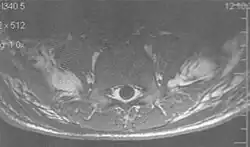

Fig. 2. Flow-related signal loss in the carotid and basillary arteries (T2 axial study of the brain).[1]

Flow can manifest as either an altered intravascular signal (flow enhancement or flow-related signal loss), or as flow-related artifacts (ghost images or spatial misregistration). Flow enhancement, also known as inflow effect, is caused by fully magnetised protons entering the imaged slice while the stationary protons have not fully regained their magnetization.[1] The fully magnetized protons yield a high signal in comparison with the rest of the surroundings. High velocity flow causes the protons entering the image to be removed from it by the time the 180-degree pulse is administered. The effect is that these protons do not contribute to the echo and are registered as a signal void or flow-related signal loss (Fig. 2).[1] Spatial misregistration manifests as displacement of an intravascular signal owing to position encoding of a voxel in the phase direction preceding frequency encoding by time TE/2.The intensity of the artifact is dependent on the signal intensity from the vessel, and is less apparent with increased TE.[1]